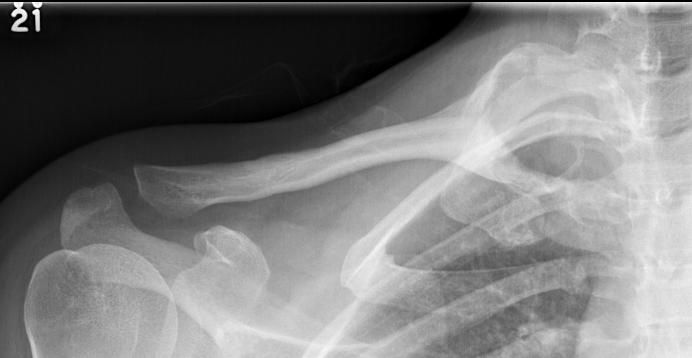

X-ray

Multi-loculated expansile lesion with cortical thickening

Often fail to make definitive diagnosis on xray

CT

ABC medial clavicle